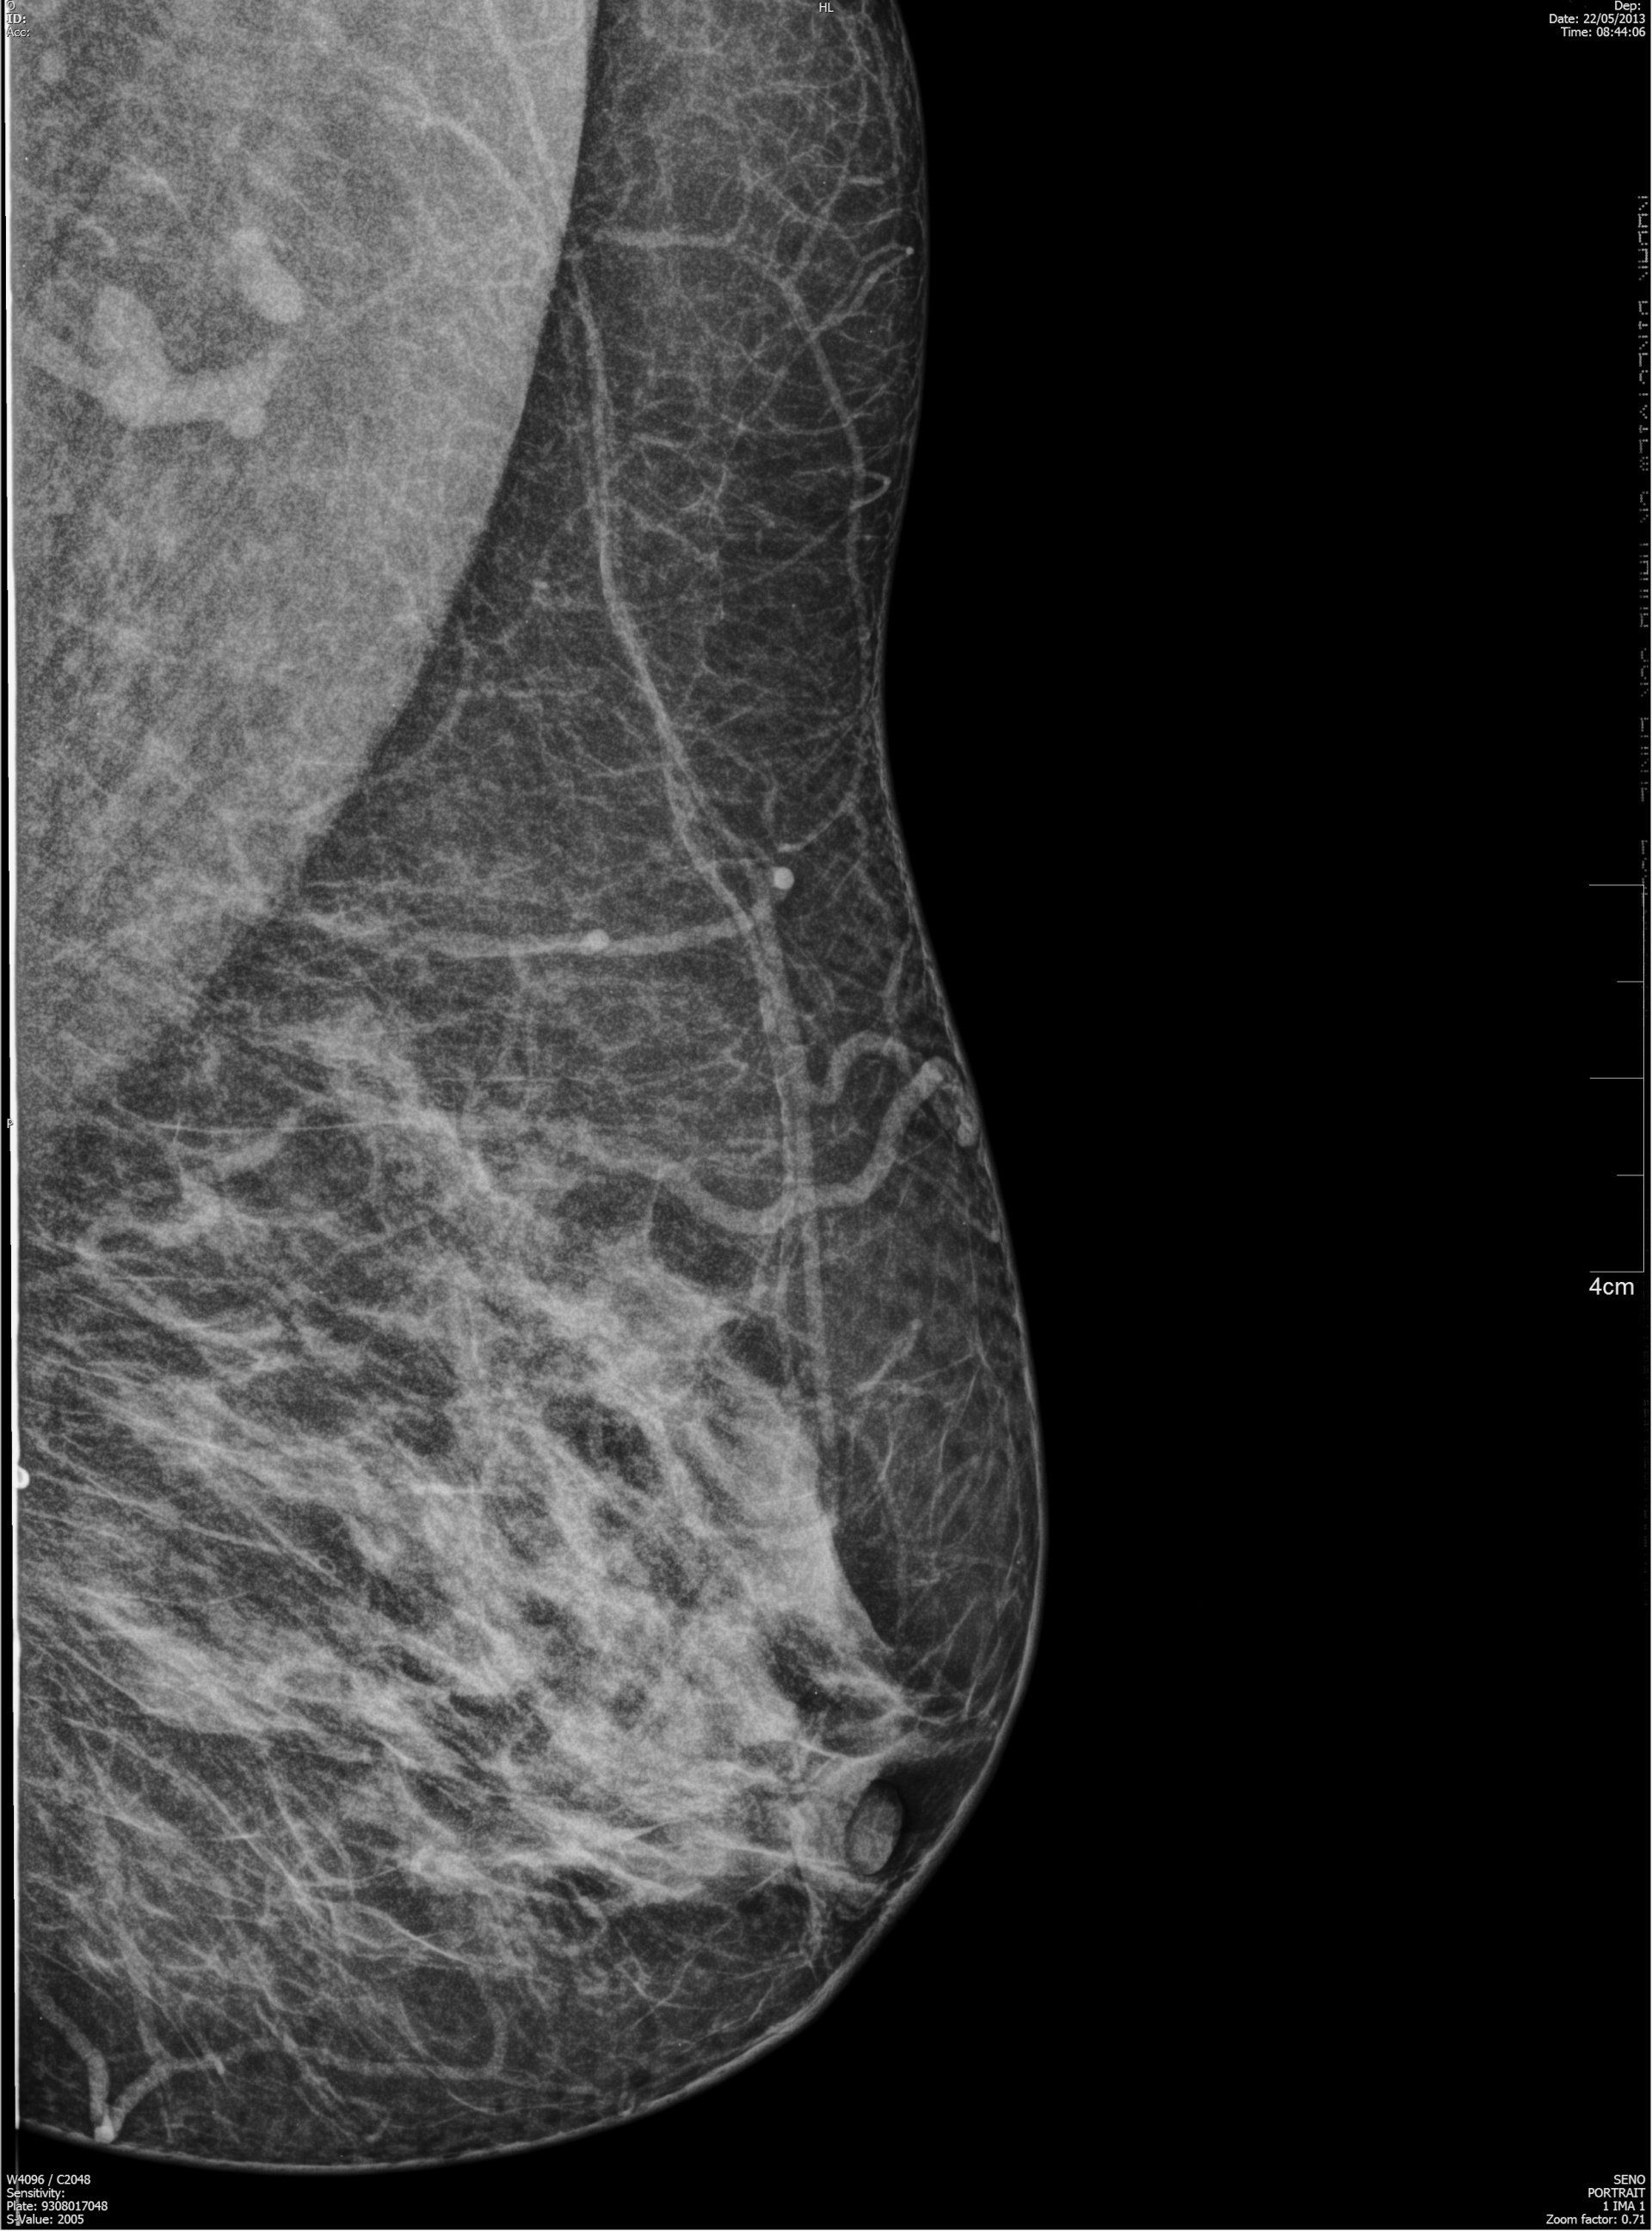

Nel Centro di Radiologia Muglia - Rago - Scaletta si eseguono mammografie accurate per donne di qualunque età che desiderano prevenire patologie al seno o tenere sotto controllo il loro stato di salute. Nella struttura è in uso un mammografo sofisticato, con esposimetro automatico che regola l’esposizione ai raggi X in funzione della densità della mammella. I protocolli internazionali consigliano l’esecuzione di un’indagine mammografica con frequenza biennale in donne in età compresa fra 39 e 50 anni. La frequenza diventa annuale tra i 50 e 74 anni.

Tutte le donne che effettuano la mammografia con tomosintesi o l’indagine ecografica della mammella presso il Centro di Radiologia Muglia - Rago - Scaletta vengono preliminarmente sottoposte a una visita senologica e al controllo degli esami precedenti. Gli esami mammografici effettuati con mammografo sofisticato della struttura vengono stampati su pellicola radiografica ad alta definizione.